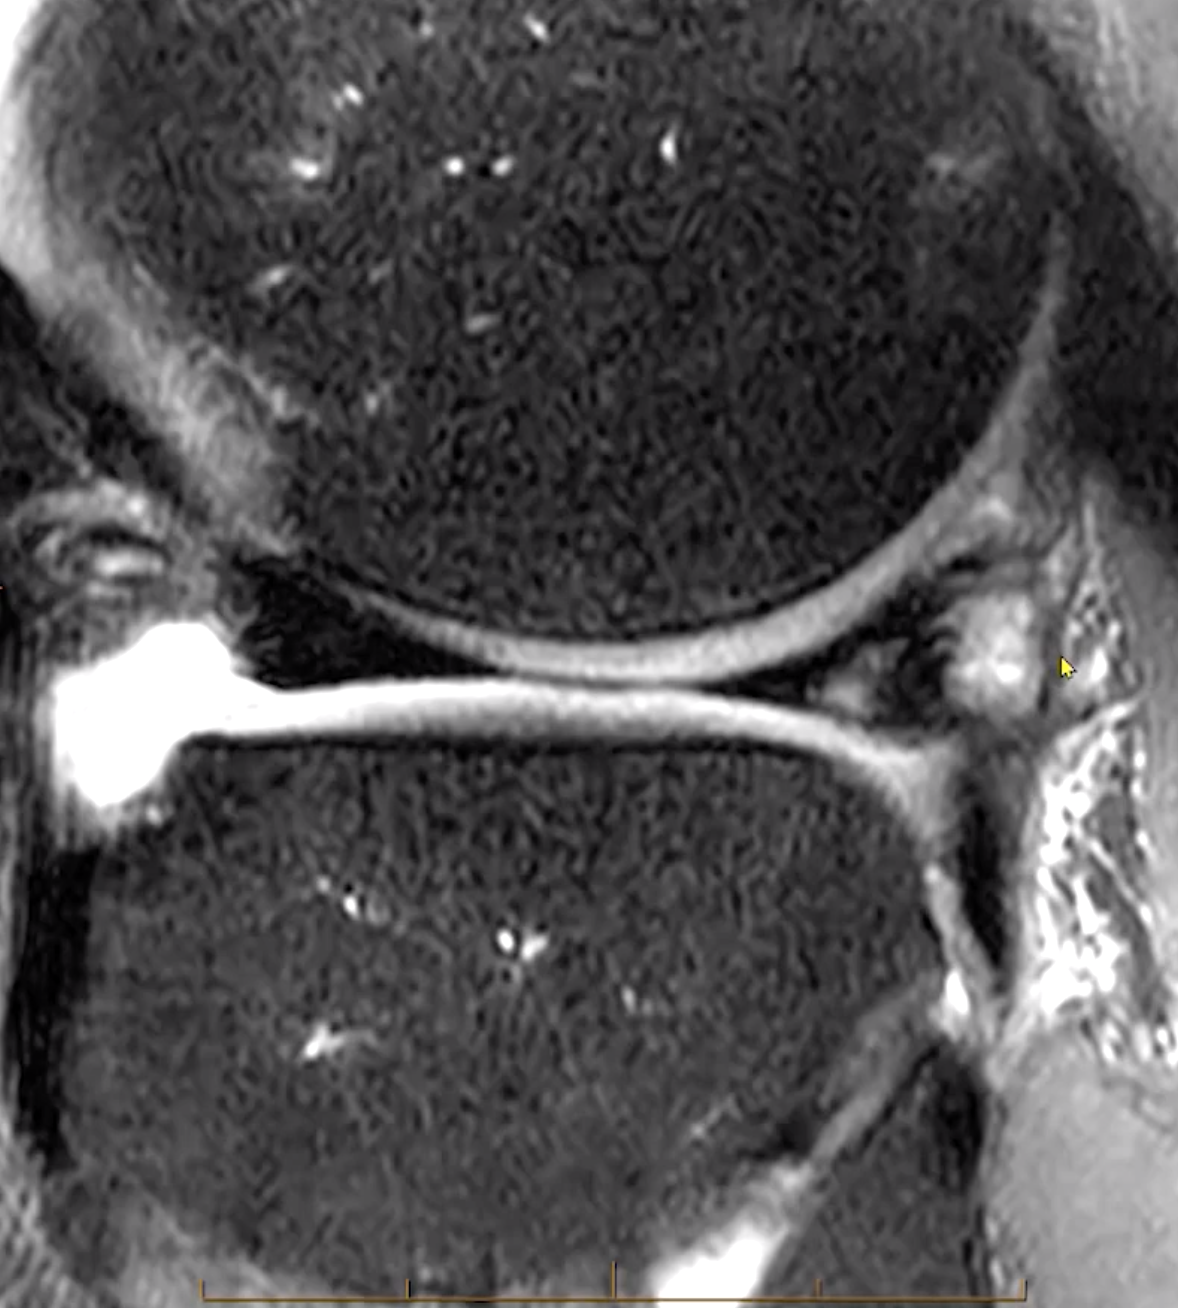

• Coronal width >14 mm or

• 3+ sagittal 5mm images

• Lateral > medial